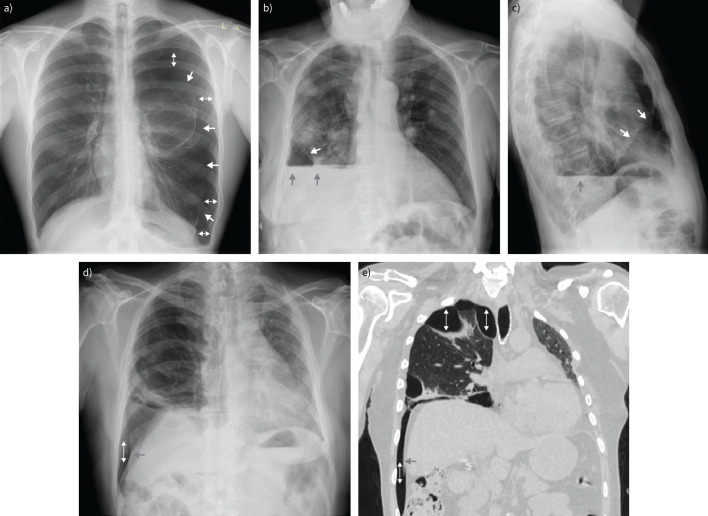

Depending on the size of pneumothorax, the lung may be completely compressed, and in cases of tension pneumothorax the mediastinum may be shifted to the contralateral side. Sometimes air may accumulate in other areas of the chest cavity as presented in figure 7. A sign that indirectly suggests the presence of air in the pleural cavity is a straight fluid horizontal line (figure 7), appearing when there is fluid and air in pleural space (hydropneumothorax).

FIGURE 7.

a) Upright, posterior–anterior (PA) radiograph with pneumothorax on the left side. White arrows show visceral pleura, which is a thin, sharply defined opaque (white) line with aerated lung (with visible vessels and lung tissue) on the hilar side. b) Chest radiograph PA view showing pneumothorax ex vacuo after pleural effusion evacuation in a patient with long-standing rheumatoid pleuritis. c) Lateral radiograph of the same patient shown in panel b. White arrows show visceral pleura of collapsed lung lobe, grey arrows show pleural effusion forming a horizontal line. d) Radiograph and e) computed tomography of the same patient with loculated pneumothorax. Thin white arrows show air in the pleural cavity. Grey arrows show deep sulcus sign.

In the case of a supine patient, air is most visible at the lung bases, increasing the lucency over the upper abdomen. Therefore, pneumothorax should be suspected when there is a sharp demarcation of the cardiac and mediastinal interfaces in anteromedial recess or there is a deep sulcus sign, double diaphragm sign or when subcutaneous gas is present in nonpenetrating trauma patients (figure 7) [60, 61]. Chest radiography in lateral decubitus position may show a small pneumothorax (15 mL of air) [62]. One should not forget about situations that may mimic pneumothorax (for details see table 1). Different formulas allow quantification of pneumothorax size and the making of therapeutic decisions (figure 6) [58, 63, 64].